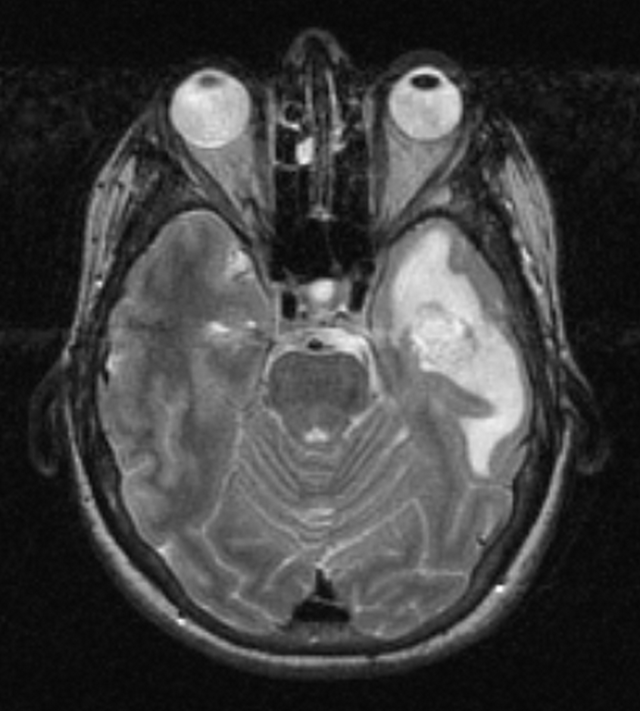

МРТ головного мозга: Расшифровка снимков и Интерпретация

Раздел: Визуальные уроки